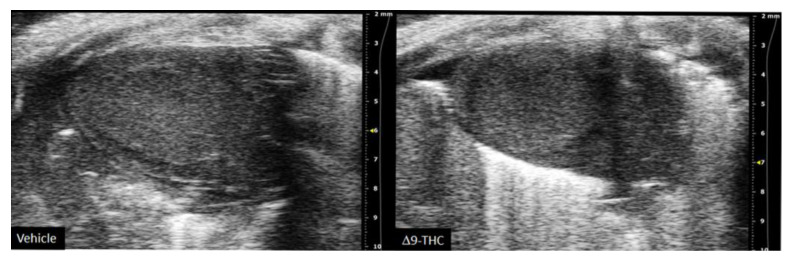

There are currently limited studies that link cannabis use in pregnancy to long-term cardiovascular dysfunction. This is crucial given prenatal cannabis or Δ9-THC alone results in FGR [ref. 9,ref. 10,ref. 11,ref. 12,ref. 67,ref. 81] and that some of the earliest work in the field of developmental origins of health and disease (DOHaD) associated low-birthweight outcomes to an increased risk of cardiovascular disease [ref. 17,ref. 18]. Furthermore, preclinical animal studies have demonstrated the adverse effects of maternal protein restriction, nicotine and hypoxia on the long-term cardiac outcomes in offspring [ref. 141,ref. 142,ref. 143,ref. 144]; however, no studies have made the link between maternal cannabinoid exposure to long-term cardiac deficits. While clinical studies demonstrate that adult cannabis use leads to adverse cardiovascular outcomes [ref. 145,ref. 146], the long-term effects of prenatal exposure remains elusive. A recent retrospective cohort study did speculate that cannabis exposure in utero might be detrimental to heart development given babies born to cannabis had an increased risk of death within 1 year of birth [OR = 1.35, 95% CI = 1.12, 1.62] [ref. 147]. However, the definitive effects of constituents of cannabis (i.e., Δ9-THC, CBD) on the developing heart warrant further investigation. Recently, we demonstrated that rat offspring exposed to Δ9-THC in utero resulted in cardiac growth deficits at birth (Figure 2) [ref. 148], followed by cardiac remodeling and impaired cardiac function at 3 weeks [ref. 148]. Specifically, at 3 weeks of age, Δ9-THC-exposed pups exhibit complete catch-up growth concomitant with early signs of ventricular hypertrophy and increased fibrotic markers, namely collagen type 1 and 3 [ref. 148]. This was associated with lower stroke volume and cardiac output. These elevated markers of cardiac hypertrophy and fibrosis have been previously demonstrated in IUGR models of maternal nicotine, hypoxia, and protein restriction [ref. 141,ref. 142,ref. 144]. While these aforementioned studies observed these effects around adulthood (3–7 months old), it is noteworthy that the Δ9-THC offspring began to exhibit deficits at 3 weeks [ref. 148]. Unfortunately, our study did not examine effects in the females, and further studies should investigate whether these cardiac deficits persist later in life.